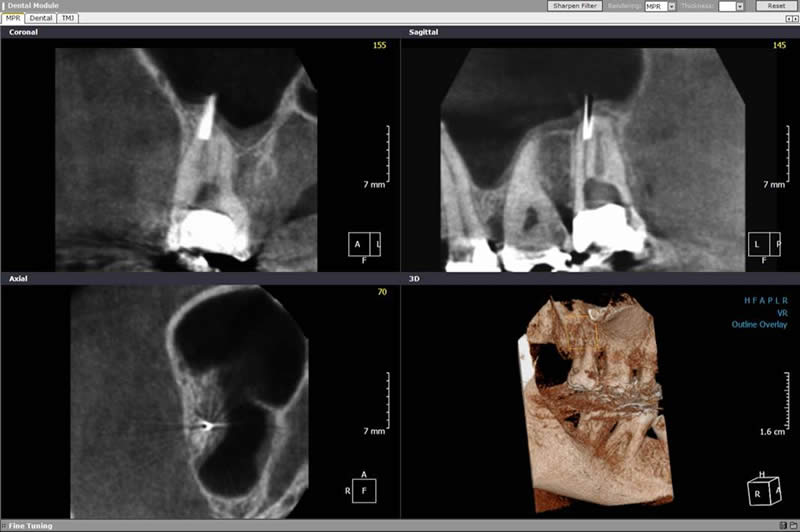

3D DIAGNOSTIK ZENTRUM BODENSEE Nebenbefund: zusätzlich im Oberkiefer Verschalung der Kieferhöhle

Neben den zahlreichen Anwendungsmöglichkeiten des DVT in der Zahnmedizin und Kieferchirurgie profitiert auch die HNO-Heilkunde von dem dreidimensionalen Verfahren.

Durch die genaue Darstellung von Nasennebenhöhlen und Schädelbasis verbessern sich Diagnostik und Operationsverfahren deutlich.